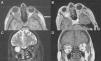

Los leiomiomas son lesiones de lento crecimiento originarias del músculo liso. La localización orbitaria solo ha sido descrita en 25 casos. Sus características histológicas y la ausencia de recurrencia tras la resección total apoyan su comportamiento benigno. Presentamos un caso de hemangioleiomioma intraconal en una mujer de 55años tratado quirúrgicamente mediante craneotomía fronto-orbitaria con resección total y sin recurrencia de la lesión tras 15meses de seguimiento. Se discuten los hallazgos histológicos y radiológicos, enfatizando en el papel pronóstico de la cirugía.

Leiomyoma are slowly growing lesions arising from smooth muscle. Orbital location has been reported in 25 cases. Histological findings and no recurrence after total resection support their benign behaviour. We report an intraconal orbital haemangioleiomyoma in a 55-year-old female treated by total resection through fronto-orbital craniotomy, with no recurrence after 15 months of follow-up. Radiological and pathological features are discussed, emphasising the prognostic role of the surgery.